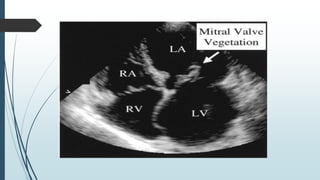

ECHOCARDIOGRAPHY

ECHO confirms and measures vegetation, detects

intracardiac complication and assesses cardiac function.

TRANSTHORACIC ECHOCARDIOGRAPHY (TTE)

Non invasive and specific

can not detect vegetation <2mm in diameter

Inadequate in emphysema and obese.

Not optimal for evaluating prosthetic valve or detecting

intracardiac complications.

TRANSESOPHAGEAL ECHOCARDIOGRAPHY (TEE)

 Safe and detects vegetation in >90% with definite IE.

 Negative TEE does not exclude IE but requires repetition in 7 – 10

days.

 Optimal for diagnosis of PVE and intracardiac complications like

myocardial abscess, valve perforation or intracardiac fistulae, and

detection of vegetations in patients with CIED.